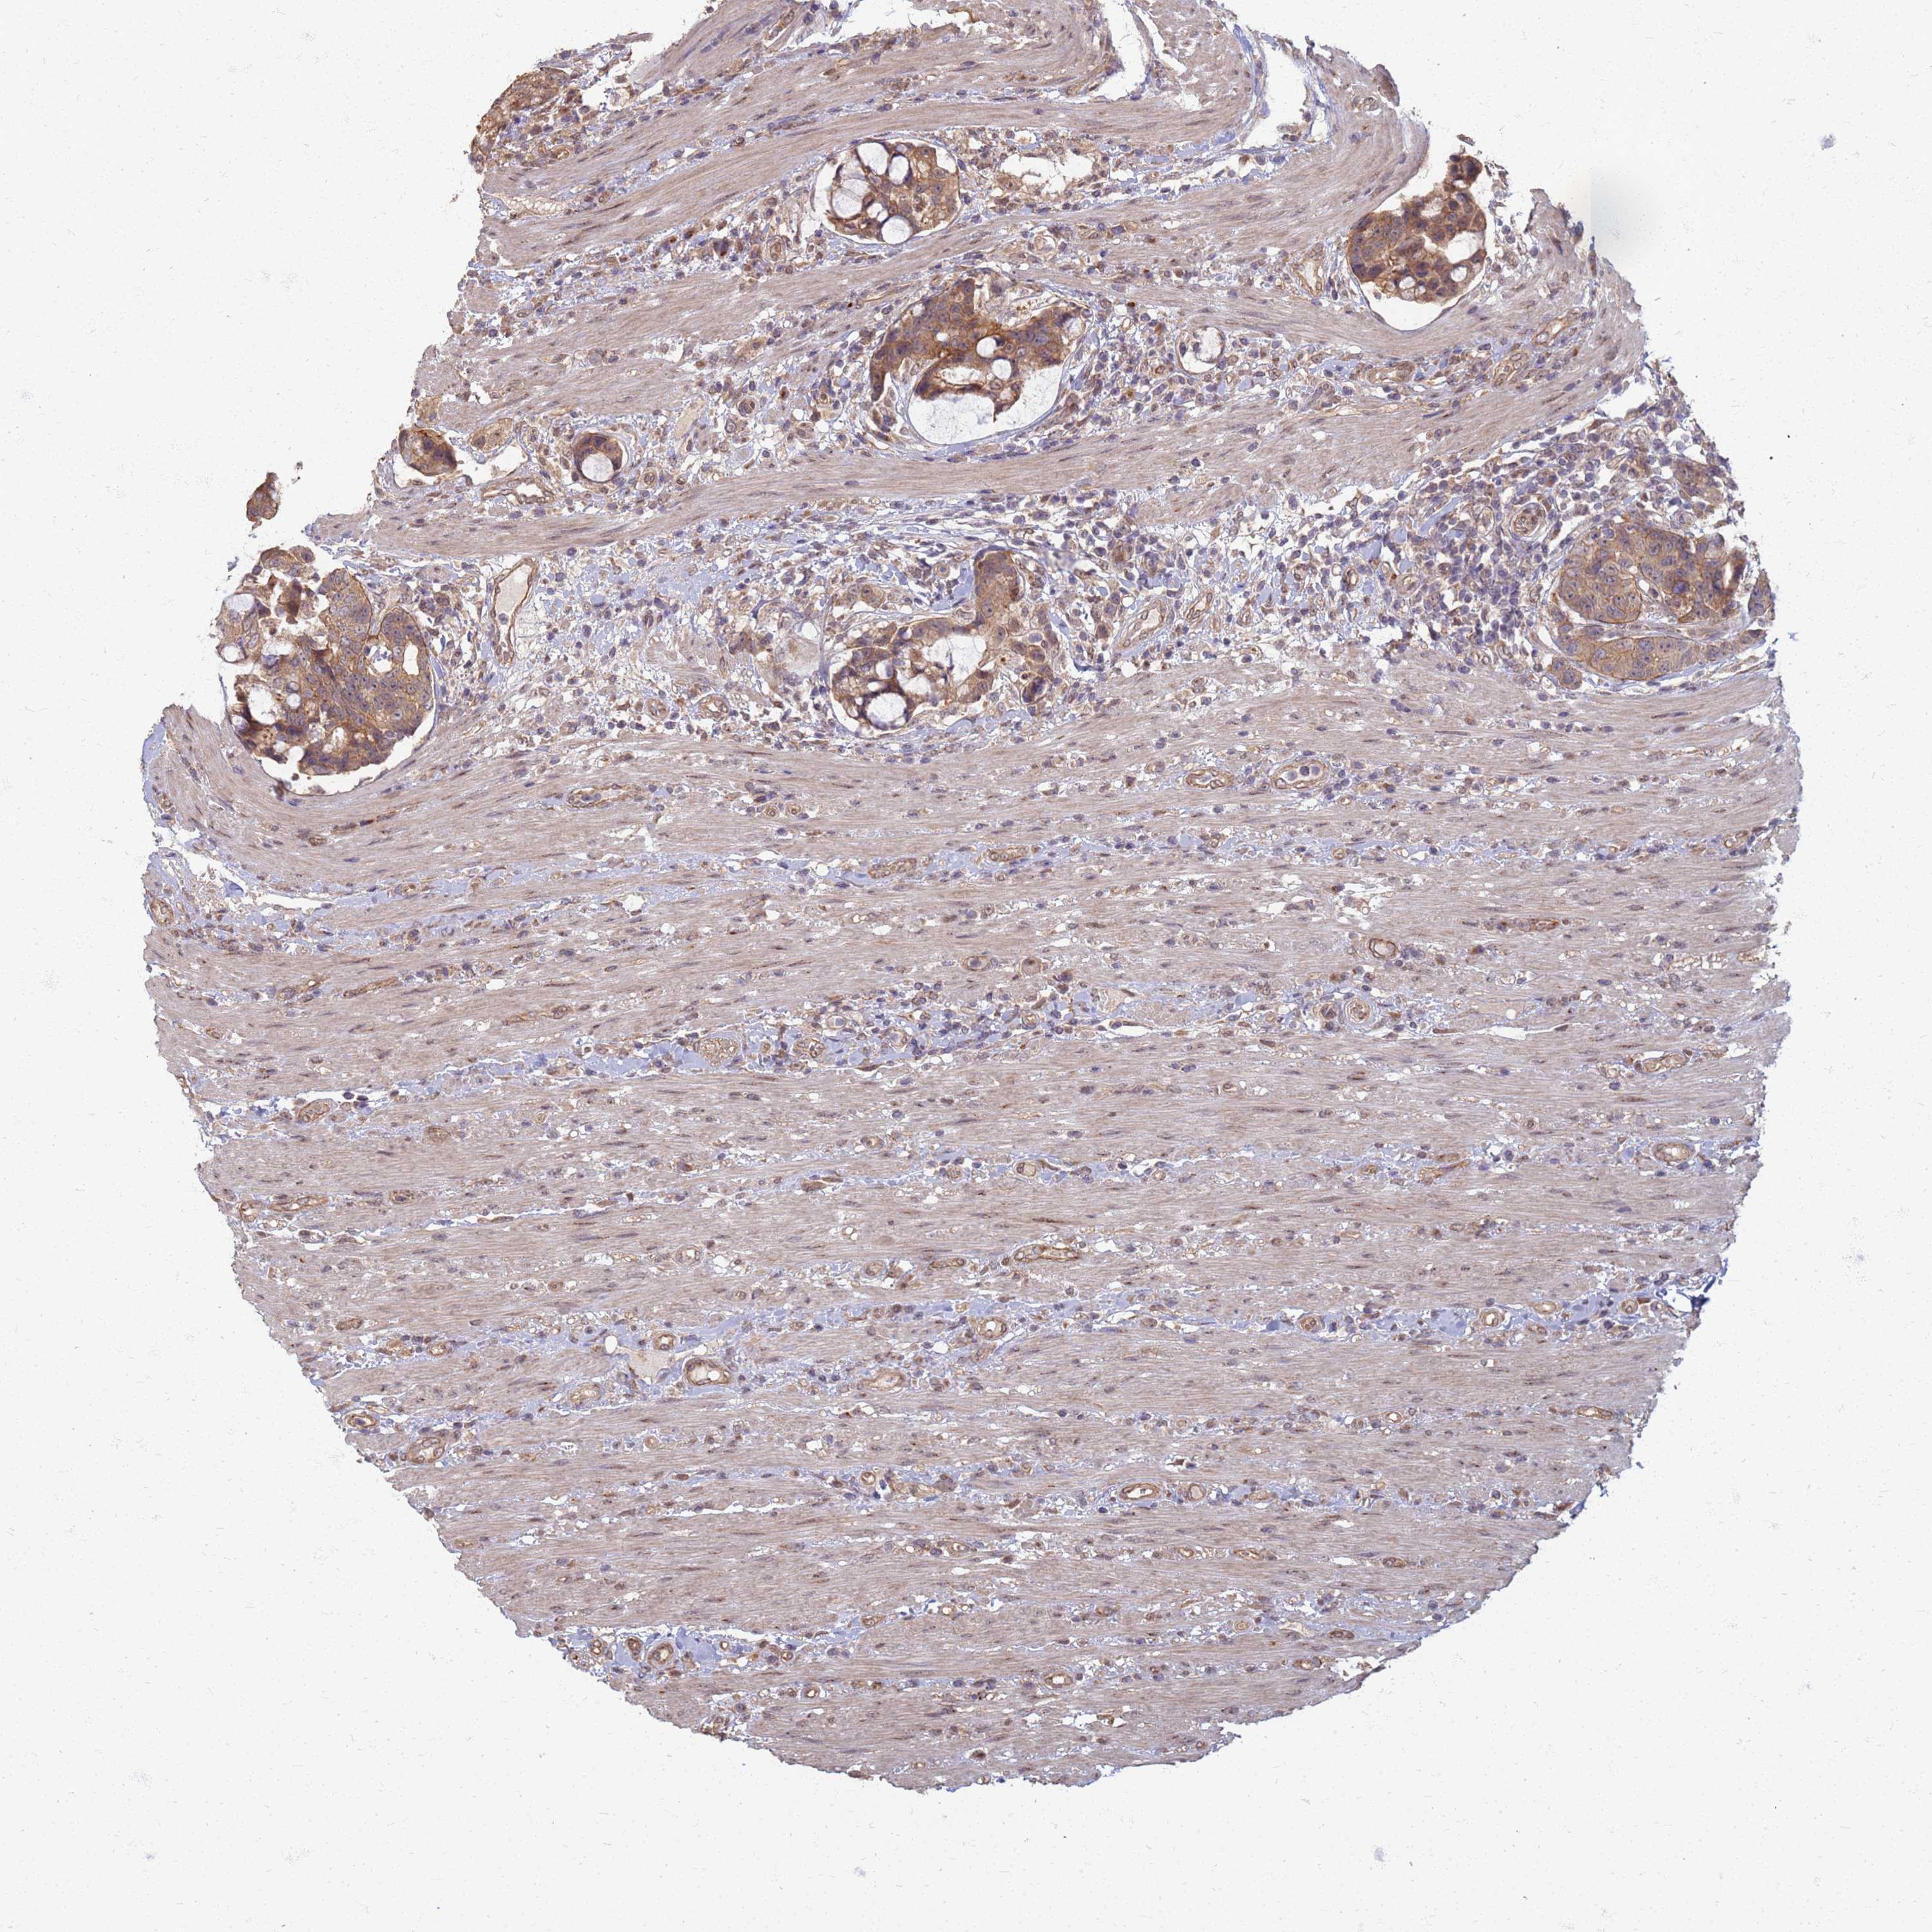

CANCER COLORECTAL CANCER Show tissue menu

Colorectal cancer

Human cancer

Rectum adenocarcinoma